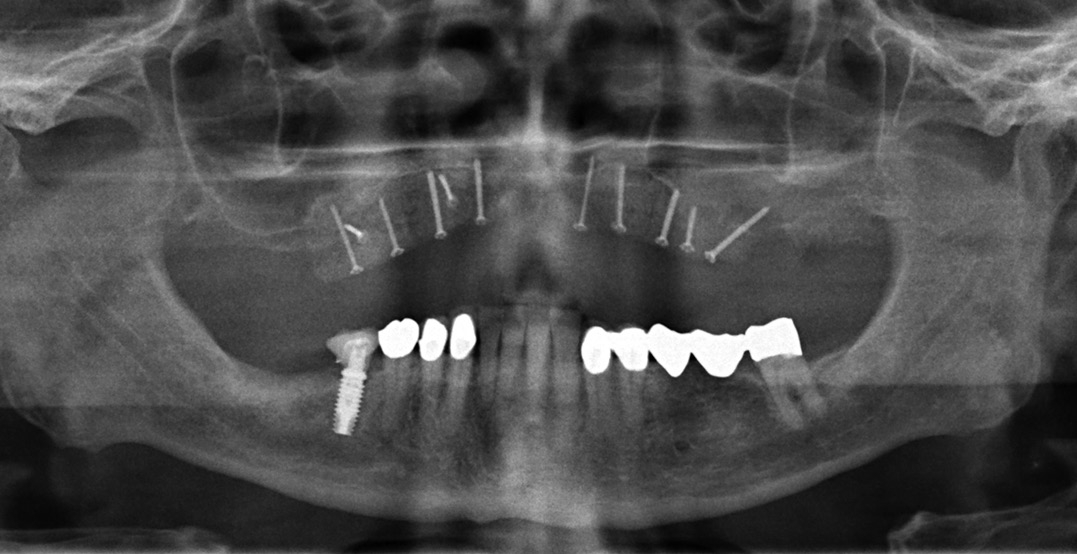

Patientenfall: Chirurgische Umsetzung

Aufgrund der hochgradigen Atrophie des Kieferknochens war für die geplante implantatprothetische Versorgung eine absolute Kieferkammerhöhung notwendig. Nach gründlicher Anamnese und Patientenaufklärung begann die Behandlung.

Die Transplantation erfolgte unter Vollnarkose (Abb. 7 bis 11). Für einen erfolgversprechenden Eingriff sind eine großzügige Mobilisierung des Weichgewebes, eine präzise Schnittführung und die richtige Nahttechnik wichtig. Das Freilegen des ortsständigen Knochens erfolgte über eine marginale Schnittführung von vestibulär. Danach wurde der allogene Knochenblock kurz in einer Einwegspritze unter Vakuum in steriler isotoner Kochsalzlösung rehydriert, um die Passage der einwandernden, azellulären Matrix durch Osmose zu verbessern. Die palatinale Gingiva wurde bis zur Raphe Median-Ebene deperiostiert. Das Fixieren der Blöcke erfolgte mit Osteosyntheseschrauben (Screw fixation 1.2, Stoma-System). Diese wurden schräg in das Transplantat bzw. den Knochen eingebracht, was vor allem bei einem dünnen basalen Knochen für eine sichere Fixierung wichtig ist (Criss-Cross-Technik). Idealerweise wählt man eine Schraubenposition, welche die spätere Implantatachse annähernd wiedergibt. Dies vereinfacht z. B. das Vorgehen bei der Schraubenentfernung.

Implantattherapie: Kurze Implantate als Ausweg

Die Implantatpositionierung war eine Herausforderung. Die Knochenblöcke haben eine durchschnittliche Höhe von 1 cm. Normalerweise wird versucht, die Implantate so zu inserieren, dass der unter dem Transplantat befindliche, ortsständige Knochen eingebunden wird. Aufgrund der relativ lockeren Verbindung des Transplantates mit dem Knochen bestand die Gefahr eines Abhebens des Knochenblockes bei der Insertion. Zudem müssen die unvermeidbaren Resorptionen am allogenen Block – vergleichbar mit natürlichem Knochen – bedacht werden, die nach Erfahrung des Autors zirka 10 bis 15 Prozent betragen [Nilius, M. in process]. Dieser Verlust ist bei der Überlegung zum Implantatsystem einzubeziehen.